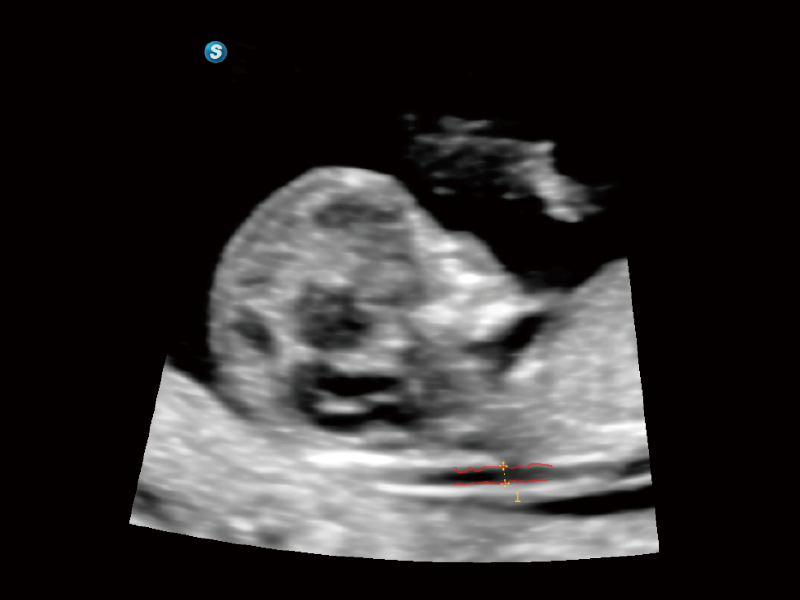

作為開(kāi)立醫(yī)療全新打造的超高端旗艦超聲產(chǎn)品,從探頭抬起喚醒開(kāi)啟掃查到多維探頭發(fā)射接收,通過(guò)先進(jìn)的場(chǎng)成像發(fā)射、自適應(yīng)聚合重建等技術(shù),基于RF Data原始射頻數(shù)據(jù)在圖像生成、高端功能等方面實(shí)現(xiàn)突破,為婦產(chǎn)科、兒科提供全方位臨床解決方案。

夢(mèng)溪?P80以“關(guān)愛(ài)女性”為基石,提供全方位的解決方案,量身定制以滿足女性的健康需求,涵蓋婦科、生殖健康檢查、產(chǎn)前篩查及產(chǎn)后康復(fù)等領(lǐng)域。